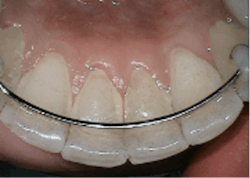

- Sodium bicarbonate powder for the removal of heavier stain supragingivally Glycine powder for supra/subgingival access with a standard nozzle that reaches PD up to 4 mm and subgingival nozzle for PD up to 5 mm.1 A flexible narrow tip is attached to the subgingival nozzle to allow for subgingival access with minimal tissue distention (figure 2).1,3,6

Air polishing conserves tooth structures with studies showing similar root effects as ultrasonics, which cause 50% less alterations, roughening, scratching, and gauging of root surfaces than hand-activated instruments.1 All glycine and erythritol air polishing powders have a very low Mohs hardness rating (2-3) and are more uniformly shaped than polish paste of any grit size, leading to less abrasivity.1,8,9